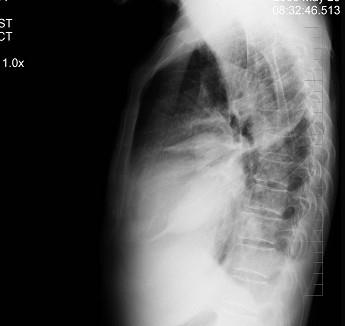

问题 患者女性,70岁,胸闷、气逼数年,无明显发热、胸痛,如图最可能的诊断是 ( )

选项 A.心包积液并右水平裂积液 B.心包积液并右下肺炎 C.心包积液并右斜裂积液 D.心包积液并右双叶间裂积液 E.气胸

答案 D